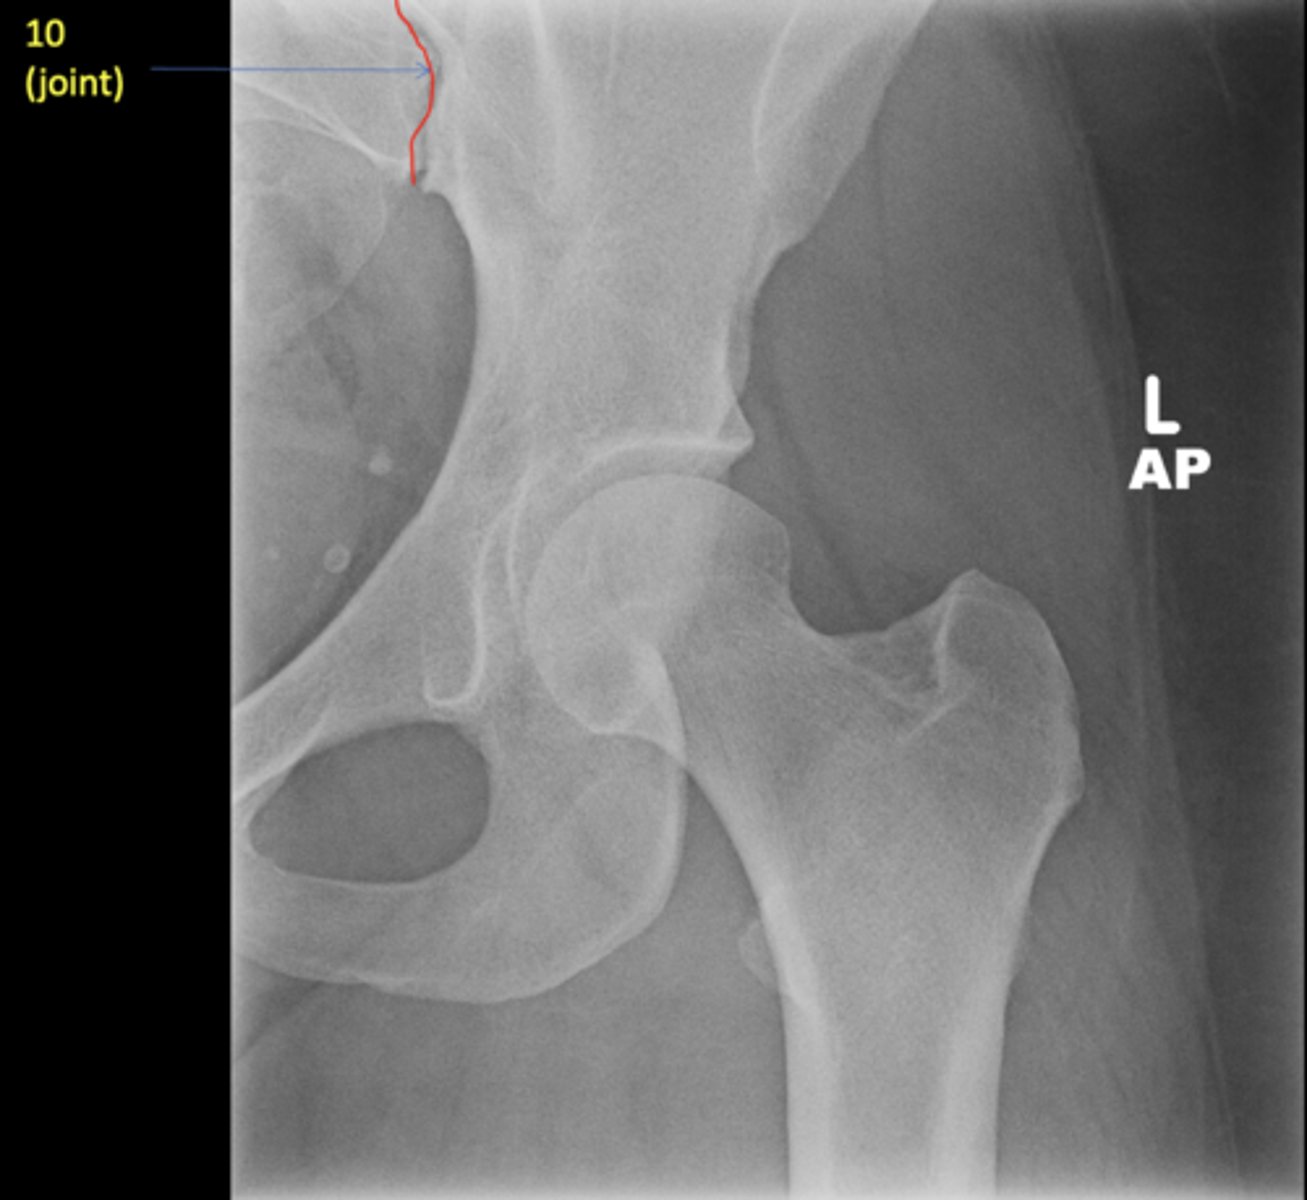

New cards

Left AP hip

View?

Sacroiliac joint

ID 10 (joint)

<p>ID 10 (joint)</p>